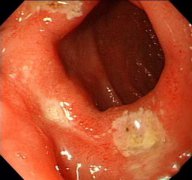

十二指腸炎是指發(fā)生于十二指腸的炎癥,分為原發(fā)性和繼發(fā)性兩種,原發(fā)性者也稱非特異性十二指腸炎。本病臨床癥狀缺乏特征性,主要表現(xiàn)為上腹部疼痛、惡心、嘔吐、嘔血和黑便,有時和十...